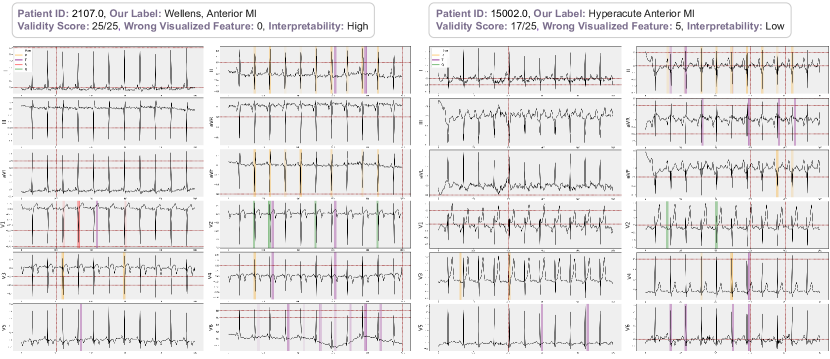

51 reports were evaluated (Figure 5); 5 of them were excluded due to extreme artifacts (n=1, =0) and ventricular extrasystole (n=4, 10.25 ± 5.5). Of the remaining 46 reports, 17 were categorized as high (23.29 ± 1.04), 14 as moderate (20.28 ± 0.99), and 15 as low (11.20 ± 7.76) in terms of interpretability. The "±" symbol represents the mean and standard deviation of validation scores, respectively. A total of 31 reports were identified as acceptable.

In the alignment of blind evaluations and identified clues, we obtained scores of 0.83 ± 0.12 for high-quality reports, 0.57 ± 0.10 for moderate-quality reports, and 0.22 ± 0.24 for low-quality reports. We observed that a many of the low-quality reports were attributed to incorrect peak detection, which inevitably resulted in their low-quality classification. Moreover, these low-quality reports often contained labels that were inconsistent with our blind evaluations and the original labels.